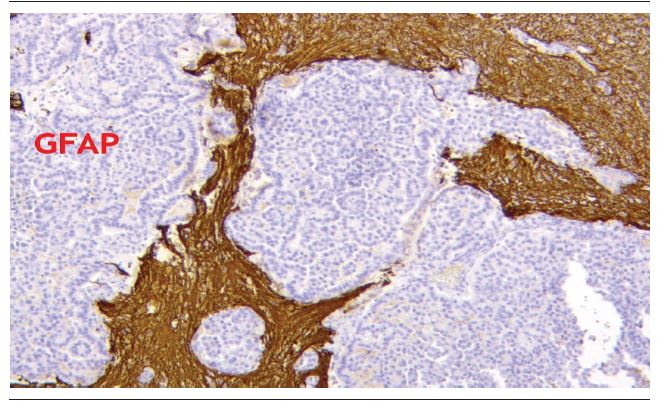

A 49-year-old female patient was admitted to a public hospital in Goiânia, Goiás, Brazil, with history of emotional stress, severe headache that began four months ago, and hypoesthesia in the lower right limb. She denied seizures, syncope and other manifestations. The physical examination revealed Glasgow scale score of 15; pupils equal and reactive to light; tactile, thermal, painful and proprioceptive hypoesthesia in lower right limb. A magnetic resonance imaging (MRI) of the brain was conducted, which identified two lesions: a hyperdense, oval, lobulated mass measuring 6.1 x 3.3 x 4.3 cm; another with a hyperdense center, lobulated contours, measuring 2 x 7.9 cm, with edema and left occipitoparietal focal mass effect (Figure 1). Both compressed the atrium and the posterior portion of lateral left ventricle. The anatomopathological study of the lesion revealed structures similar to the normal choroid plexus, with increased cellularity, presence of vascular bundles and formation of papillary structures of cubic and elongated cells (Figure 2). The general aspect of the lesion is homogeneous, revealing the benign character of the neoplasia. The immunohistochemistry (IHC) demonstrated negative cells for AE1/AE3 (Figure 3) and glial fibrillary acidic protein (GFAP) (Figure 4) and diffusely positive for epithelial membrane antigen (EMA) (Figure 5). Those results confirm the diagnosis of CPP

The markers GFAP and AE1/AE3 present negative immunoreactivity, while EMA is diffusely present in certain areas of the lesion(6). Other used markers are the exchanger regulatory factor Na+/H+1 (NHERF1), and neurofibromin 2 (NF2)(13), because they reveal higher sensitivity and specificity in the diagnosis of papillary tumors of the nervous system. The differential diagnoses of the case include metastatic carcinoma and the papillary variant of ependymoma. Treatment is based upon total surgical excision, with a five-year survival of practically 100%(5). The main surgical complication is intraoperative bleeding(2).